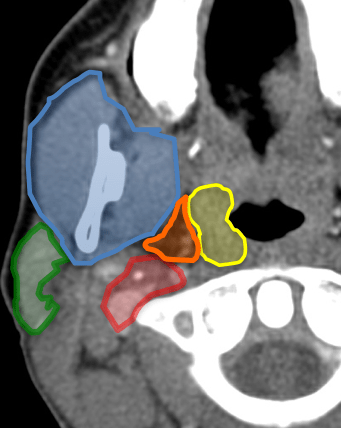

Amarillo: mucosa faringea/amígdala.

Rojo: espacio vascular.

Azul: espacio masticador.

Verde: espacio parotídeo.